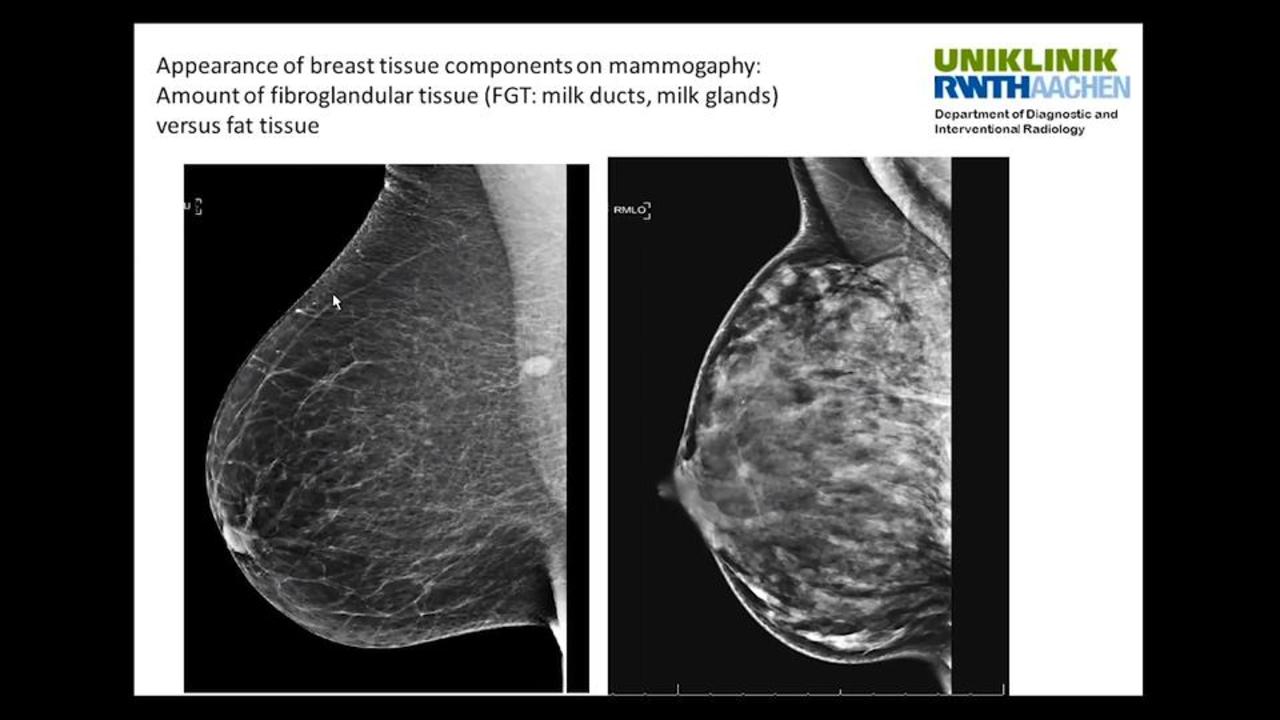

Calcifications are small deposits of calcium that show up on mammograms as bright white specks or dots on the soft tissue background of the breasts The calcium readily absorbs the Xrays from mammograms Calcifications typically don't show up on ultrasounds, and they never show up on breast MRIs Calcifications are a frequent finding onDense breast tissue is composed of less fat and more connective tissue, which appears white on Xray images created with mammography—the frontline tool of breast cancer screening Cancer also appears white on a mammogram, and if cancer is present, the tumors often are hidden behind the dense tissue Heterogeneously dense Most of the breast is dense tissue with some areas of fat Extremely dense The breasts have almost no fatty tissue

The breast tissue is heterogeneously dense, which may obscure small masses (40% of women) The breast tissue is extremely dense This may lower the sensitivity of mammography (10% of women) Approximately 50% of women undergoing screening mammography are classified as having either "heterogeneously dense" or "extremely dense" breasts Breast tissue Breast are made of milk ducts, supportive tissue and fatty tissue Women with dense breasts have a higher ratio of supportive tissue to fatty tissue Women with dense breasts have a higher ratio of supportive tissue to fatty tissueCertain diseases, such as breast cancer, can change the characteristics of the breast parenchyma Stroma is the scientific term for all of the tissue on the breast that is not part of the parenchyma This is the fatty and connective tissue that gives the breast volume, and also provides an essential blood supply to the parenchymal cells of the breast

Radiologists use mammogram images to grade breast tissue based on the proportion of dense to nondense tissue According to the BIRADS reporting system, the levels are (from left to right) almost entirely fatty, scattered areas of fibroglandular density, heterogeneously dense and extremely dense Class C (or 3) Heterogeneously dense; "Comparing women with extremely dense breast tissue to those with fatty breasts, we find a four to six times increased risk for breast cancer Women with heterogeneously dense breasts have about